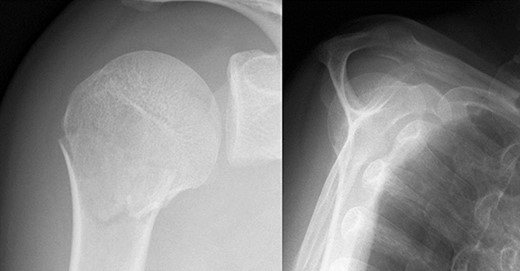

A 39-year-old man was transported via ambulance after being hit by a car. The radiographs revealed a one-part proximal humeral fracture with displacement at the surgical neck (Fig. 1). However, computed tomography (CT) revealed humeral head impression fracture and lesser tuberosity fracture in addition to a surgical neck fracture (Fig. 2). In addition, 3D-CT revealed that the collapse occupied approximately 20% of the articular surface with no glenoid defect (Fig. 3). Therefore, we first performed arthroscopic-assisted reduction and internal fixation of the humeral head impression fracture, followed by open reduction and internal fixation (ORIF) of the proximal humeral fracture.

Original CT scan showing impression fracture and surgical neck fracture.